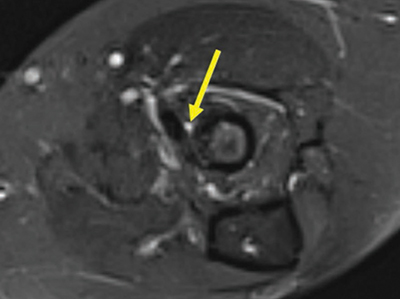

Figure 6

Coronal fat-saturated T2-weighted image at the level of the biceps tendon insertion with an irregular T2-hyperintense signal within, score 2.

Three patients (1.5%) had an altered signal intensity in the biceps tendon. One patient had a score of 1 (Figure 5), and the other two had a score of 2 (Figure 6).

Only a small percentage of patients (1.5%) had abnormal signal intensities in the biceps tendon. This prevalence is in line with earlier reports [10, 11].